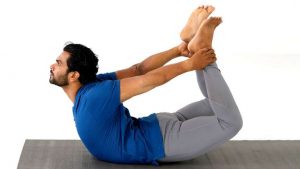

DHANURASANA ( BOW POSE):

It helps to strengthen whole abdominal organs thus improving digestion and prevents constipation. It helps in prevention of disease by improving elimination through intra-abdominal pressure.

STEPS:

- Lie down on your stomach while placing feet slightly apart, parallel to hips and arms on the sides of body.

- Slowly fold your knees up and hold ankles with your hands to stabilized the pose.

- Take deep breaths and slowly lift the chest off the floor and pull legs toward your back

- Hold the posture for few seconds

- Slowly exhale and return to initial position

PRECAUTIONS :

- High blood pressure

- Headache

- Migraine

- Insomnia

- Hernia